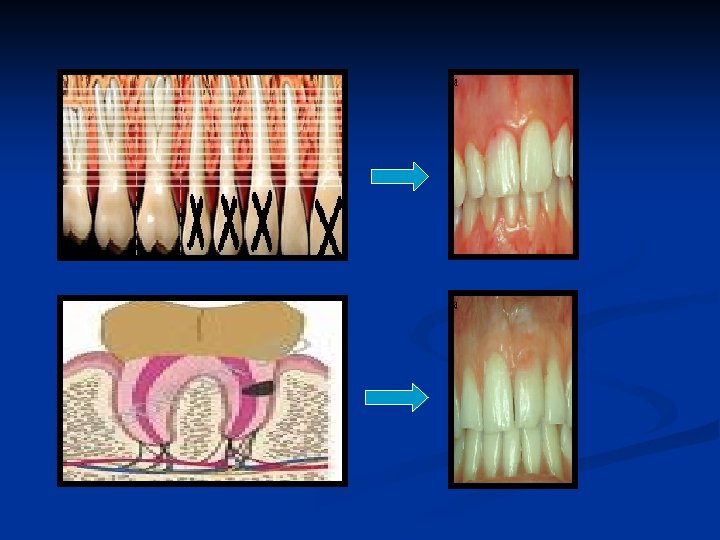

E-Ortodontik tedavide uygulanan aşırı mekanik kuvvetler: Ortodonti ile ilişkili kök rezorpsiyonu eksternal apikal kök rezorpsiyonudur. Eksternal apikal kök rezorpsiyonu, ortodontide en sık karşılan iatrojenik durumdur ve ortodontik tedavi eksternal apikal kök rezorpsiyonunun en yaygın nedenidir. Ø Lupi ve arkadaşlarının en az 12 aylık bir sabit ortodontik tedavi süresi sonunda maksiller ve mandibuler kesici dişlerde oluşan apikal kök rezorpsiyonunu değerlendirdiği çalışmalarında, incelenen dişlerin %15 ‘inde tedavi öncesi apikal kök rezorpsiyonu mevcut iken, tedavi sonunda bu oran %73’e yükselmiştir. Tedavi öncesi dişlerin sadece %2’sinde orta dereceden şiddetliye değişen rezorpsiyon rapor edilmiştir, tedavi sonunda dişlerin %24. 5 ‘u bu şiddette rezorpsiyon göstermiştir.